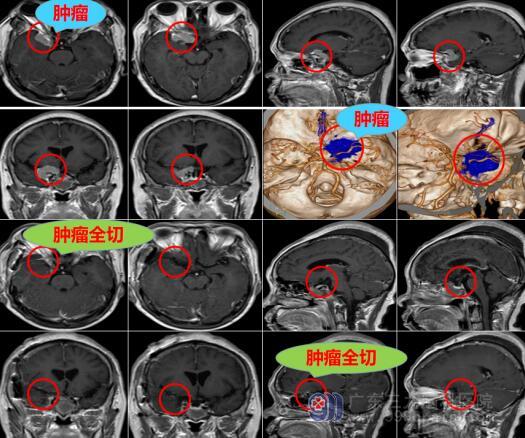

欧阳辉教授接诊了黄奶奶,进行一番详细的检查后,告诉黄奶奶及她的家人,这是由于脑袋长了鸽子蛋大小的肿瘤,肿瘤正好就压迫到视神经,从而导致出现视力下降的情况。要解决肿瘤的压迫,可以采取手术切除,肿瘤切了,右眼视力或许还有挽救的可能。

神经外十科医疗团队通过多次商讨,为黄奶奶制定了严密的手术方案。11月10日,黄奶奶被推进了手术室。手术很顺利,经过八个小时的奋战,肿瘤全切。黄奶奶被送往监护室严密观察一天,第二天便转回普通病房。目前黄奶奶手脚活动有力,最让人惊喜的是右眼比手术前看的清楚一些。